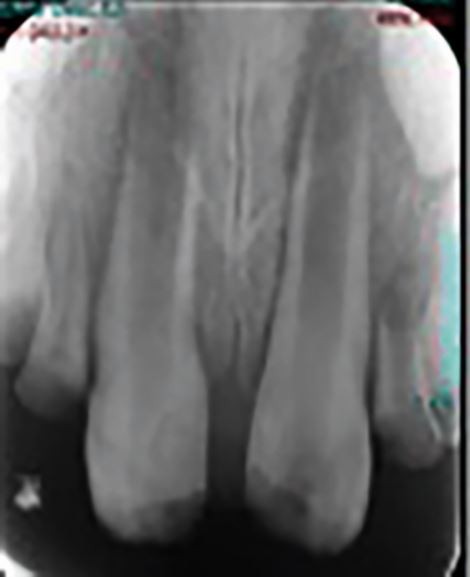

Pulp canal obliteration

Pulp canal obliteration (PCO) occurs due to the accelerated deposition of hard tissue within the pulp chamber and is evident in 3.5-64% of cases of TDI.29,30,31,32 Active deposition of tertiary dentine within the tooth aims to narrow the pulp chamber and reduce the risk of pulpal necrosis. PCO can cause discolouration which may cause aesthetic concerns and there is a risk of pulpal necrosis in 7-27% of cases.31 Prophylactic endodontic treatment is not advised in these discoloured teeth unless there are clear symptoms of periapical periodontitis.33 PCO and subsequent necrosis can prove challenging for the treating clinician to manage due to the reduced pulp space. Cone beam computed tomography (CBCT) investigation can be very helpful and referral to a specialist is often advised.

Tooth discolouration

Teeth that have sustained a TDI can discolour as a result of injury or intervention. Tooth discolouration can impact a person's self-confidence, perceived physical attractiveness and employment prospects, and may lead to negative social judgement between children.44,45 The colour of a traumatised tooth will be impacted by the pathological process occurring within the tooth. Pulpal necrosis can result in a grey discolouration occurring due to haemolysis of red blood cells and pulpal remnants within the tooth, which can penetrate the dentinal tubules.46,47 Discolouration is often noted at 4-24 months post-injury.48 PCO can result in a yellow hue due to the extra deposition of dentine within the tooth.31 Cervical root resorption is noted as a pinkish hue developing in the cervical region due to the presence of vascular tissue.34 Tooth discolouration following a TDI may also be transient due to temporary disruption of the blood supply to the tooth, or permanent, and may follow intervention eg resulting from bismuth oxide in mineral trioxide aggregate.43,49